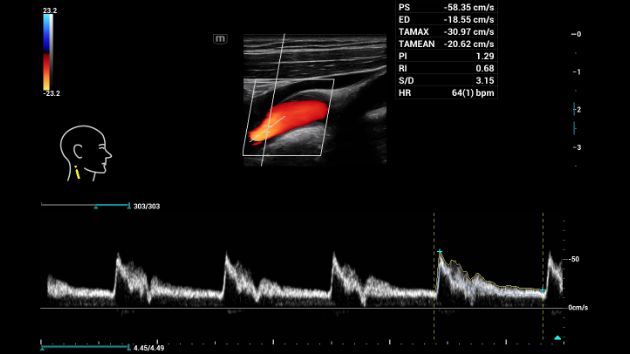

Strumento di tracciamento, misurazione e calcolo automatico

Riduce i tempi di misurazione tramite la tracciatura automatica dello spettro. Migliora la precisione e la riproducibilità del tracciamento dei margini spettrali.

Consona Series Cardiovascular Solution - Smart Calc feature clinical image